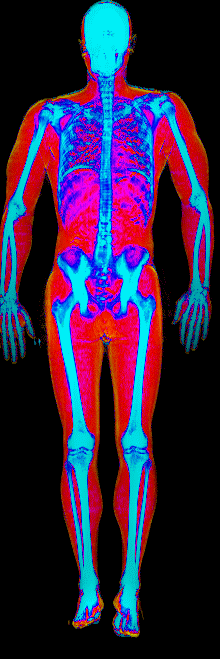

This page features real, anonymized DEXA scan images from BodyStats clients, organized by gender and body fat percentage in 5% increments. DEXA (Dual-Energy X-ray Absorptiometry) is the clinical gold standard for measuring body composition — far more accurate than scales, calipers, or visual estimates.

Each colorized scan shows the distribution of fat tissue (shown in warmer colors) and lean tissue (cooler colors) throughout the body. Compare your own DEXA scan to others in your range, or see what different body fat levels actually look like on a scan.

Male DEXA Scans by Body Fat %

10 to 15% body fat